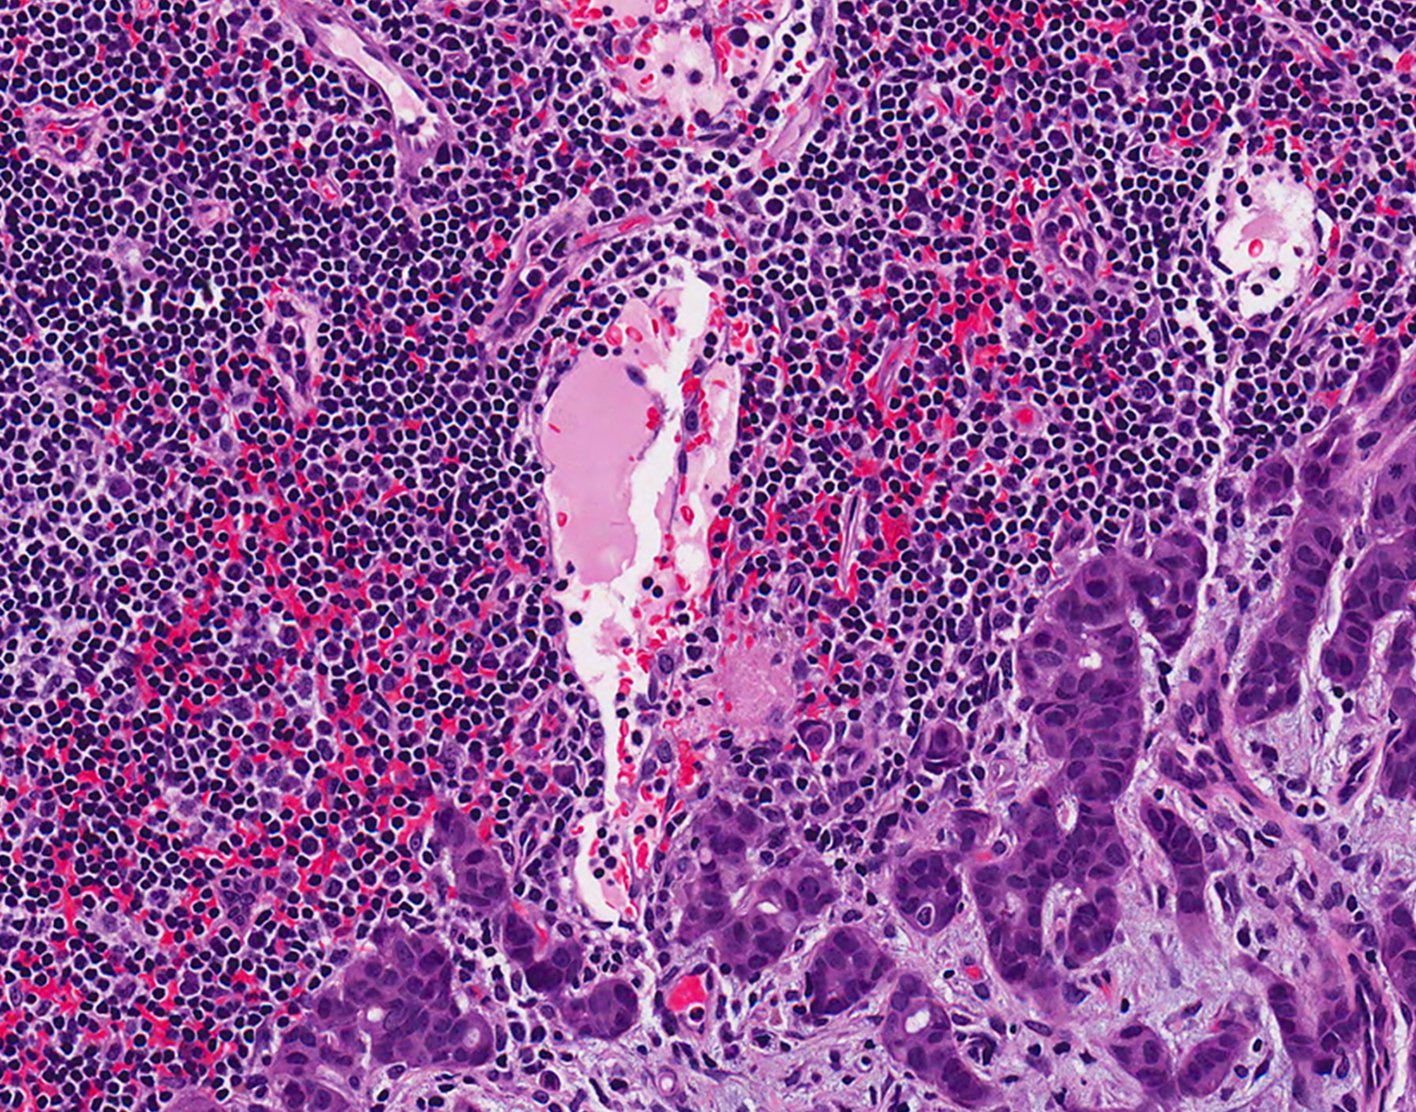

To determine whether someone has breast cancer, a biopsy must be done. Tissue from the abnormal area is removed and examined under a microscope.